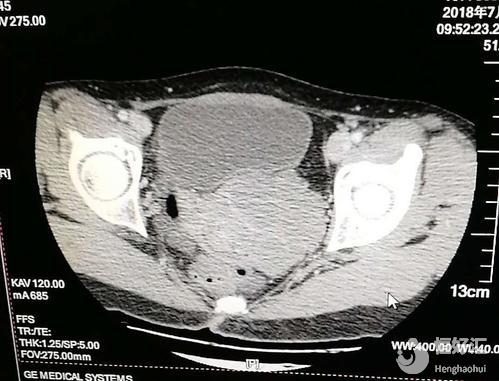

2、B超檢查:通過B超檢查可以清楚地顯示雙子宮和一側子宮積血宮頸擴張,對診斷也有很大的作用,同時還能提示一側腎臟的具體情況;

其實,如果對該疾病有充分的認知,還有一定的了解,那么診斷并不困難。而診斷陰道斜隔最正確的方法就是B超檢查,根據B超檢查的精細準確,可以提示雙子宮、雙宮頸和一側子宮頸的擴張積血,并且提示同側腎臟的缺如,對疾病確診也有很大的幫助。